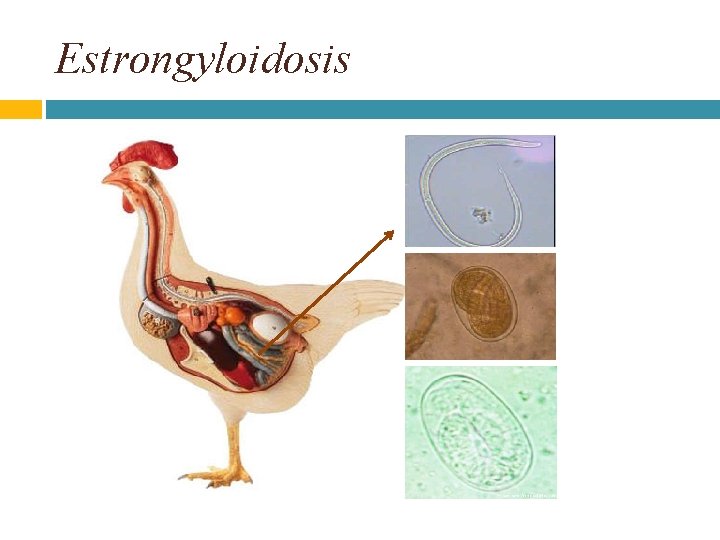

Estrongyloidosis

Morfología: Las hembras parasitas de S. avium tienen una longitud de 2. 2 mm y el esófago que es fusiforme llega casi a la mitad del cuerpo (0, 7 mm), sus huevos están embrionados.

Ciclo Biologico larvas no poseen la vaina del segundo estado y son capaces de infectar al hospedador penetrando a través de la piel y las mucosas, tras la cual llegan al intestino delgado y completan el ciclo en 5 -7 días. En el intestino delgado de los hospedadores la hembras, de solo algunos milímetros de longitud constituyen la forma parasitaria que se produce por partenogénesis penetran el epitelio intestinal y se localizan en la lamina propia, su conformación cromosómica es triploide, pone huevos larvados, de cascara fina y transparente L 3 las larvas que nacen pueden continuar su desarrollo hasta larvas 3 e infectar a otro hospedador o dar lugar en 48 horas al desarrollo de macho adultos de vida libre y hembras adultas de vida libre, las que copulan varias veces